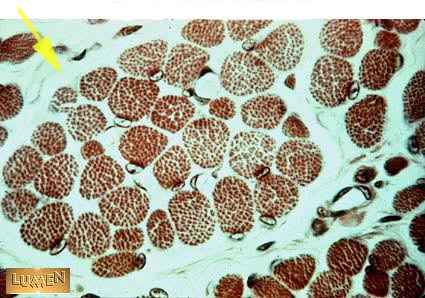

Name this connective tissue delineated by the arrow.

Perimysium